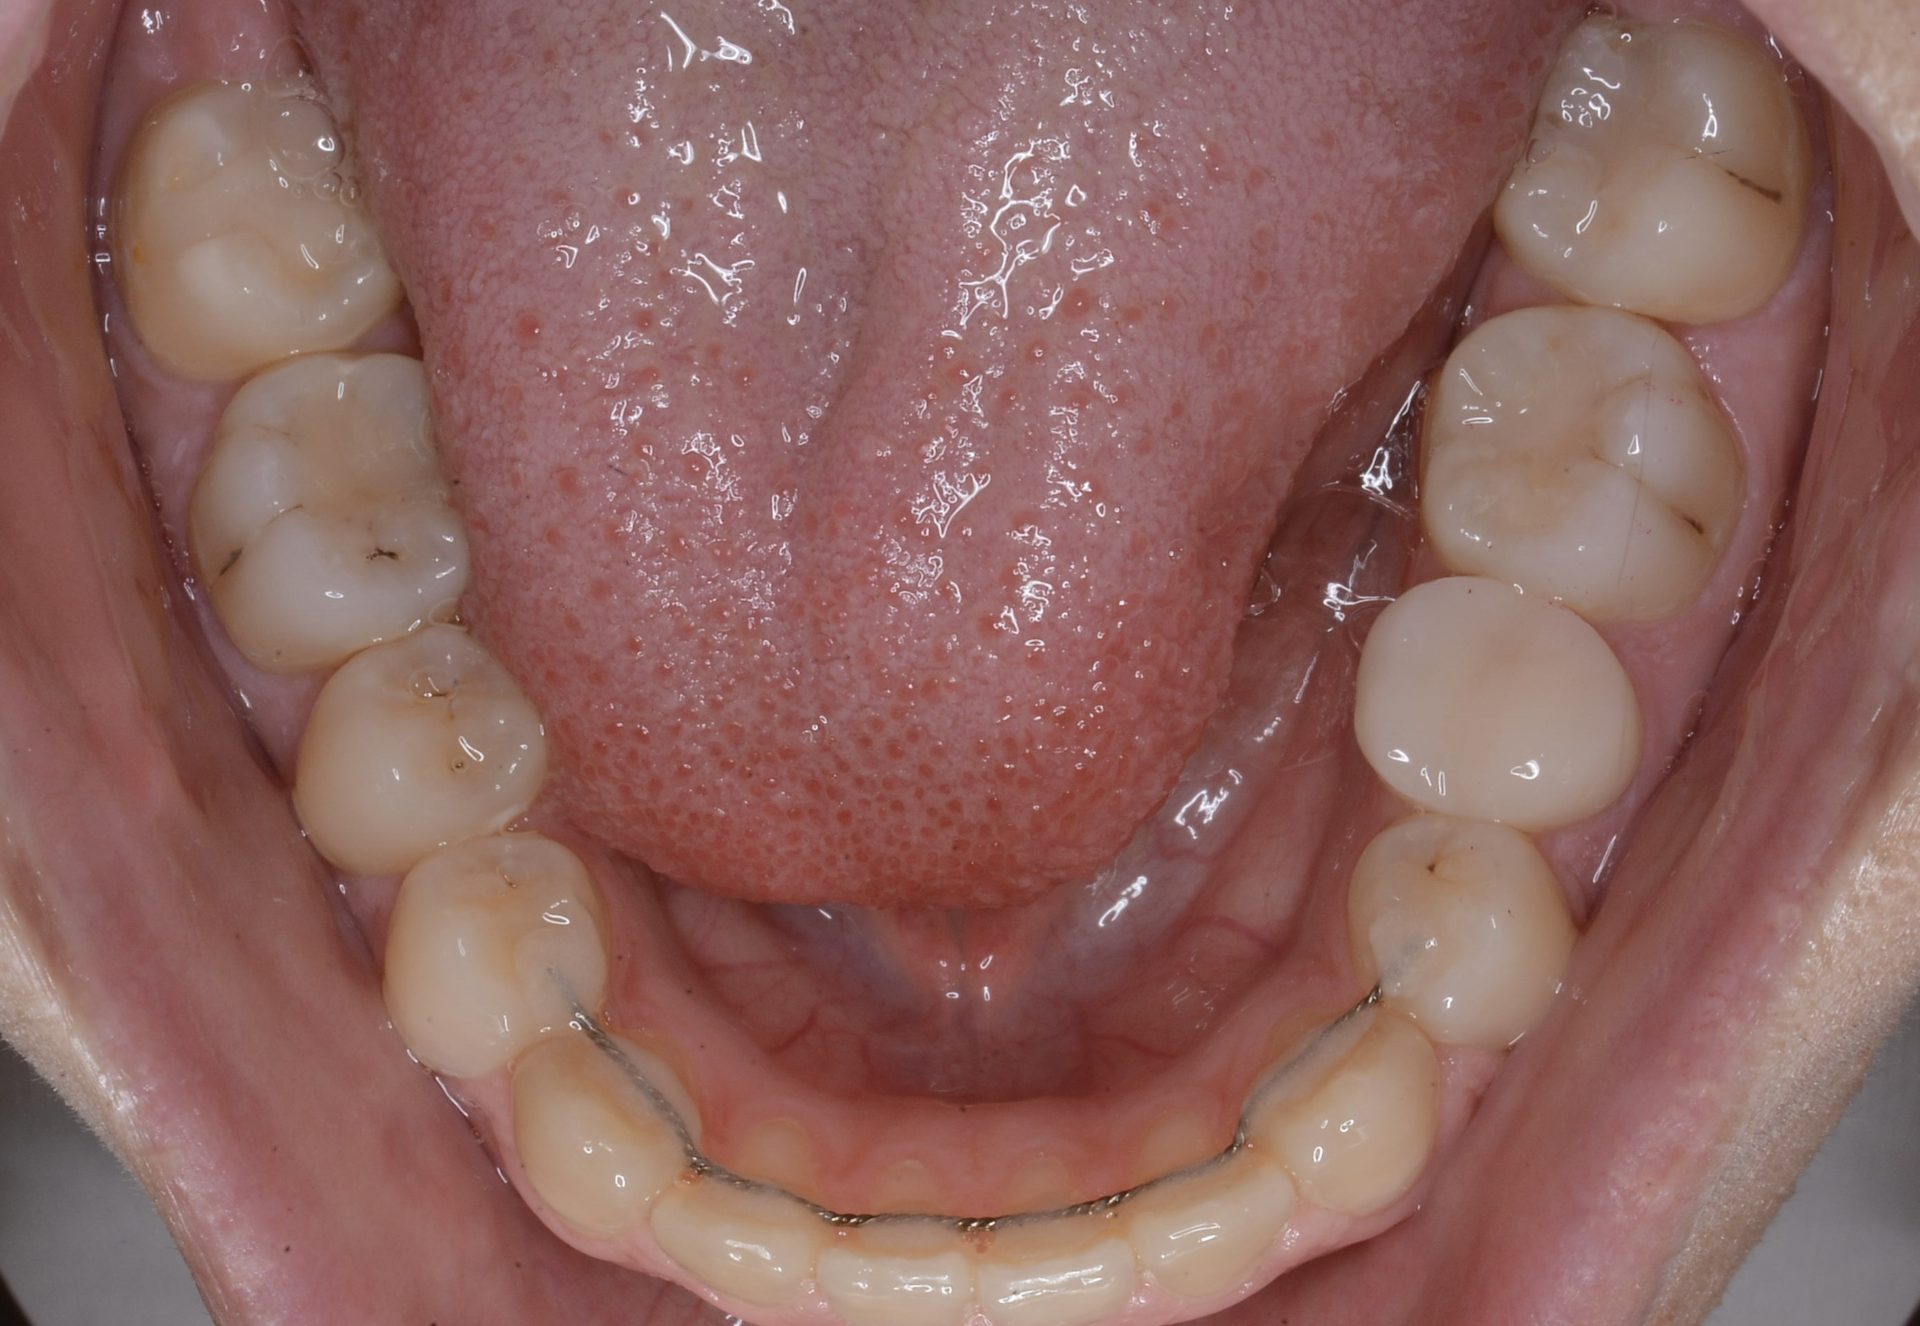

矯正治療スタート時(下顎)

初診時(下顎)10代の若さですでに左下第2小臼歯の神経の処置がしてあり大きな金属冠が入っている。前歯が噛んでいないことにより臼歯部の負担が強く歯にひびが入り、虫歯が進行してしまったと思われる。

メインテナンス時(下顎)